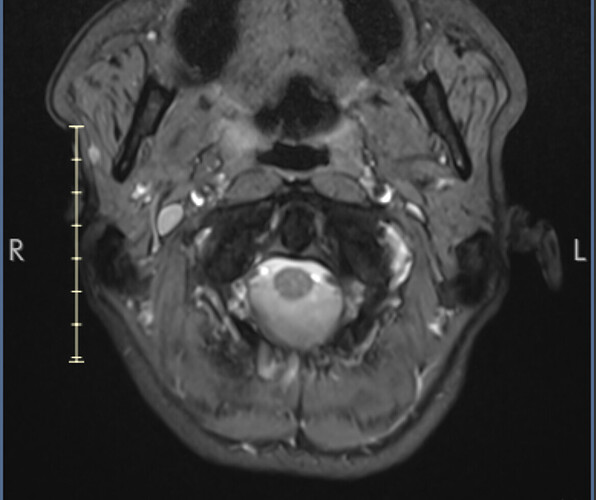

First stage of diagnosis - MRI images

I’ve uploaded some images now. I know they aren’t ideal but I’ll hopefully get my hands on the CT angiogram I had at A&E soon.

I marked the images for you and marked the IJV.

So you can see how the IJV passes by the transverse processes of C1 which are compressing. In this position the right IJV does not have severe compression, but in Figure 2 you can see that the left IJV is almost invisible, and in the other images there is significant narrowing.

On MRI, it is very difficult to see the styloid processes.